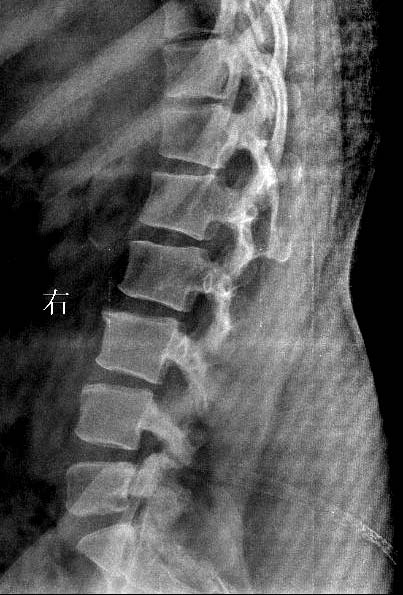

女.29岁.先天髋关节脱位.腰椎后部向外膨出.外院诊断骨肉瘤.我院诊断夏科氏关节病。

女.29岁.先天髋关节脱位.腰椎后部向外膨出.外院诊断骨肉瘤.我院诊断夏科氏关节病请大家讨论!

支持:1、脊柱裂;

支持:1、隐性脊柱裂;

1、脊柱裂;伴脊髓脊膜膨出?建议mri检查,

脊柱裂;